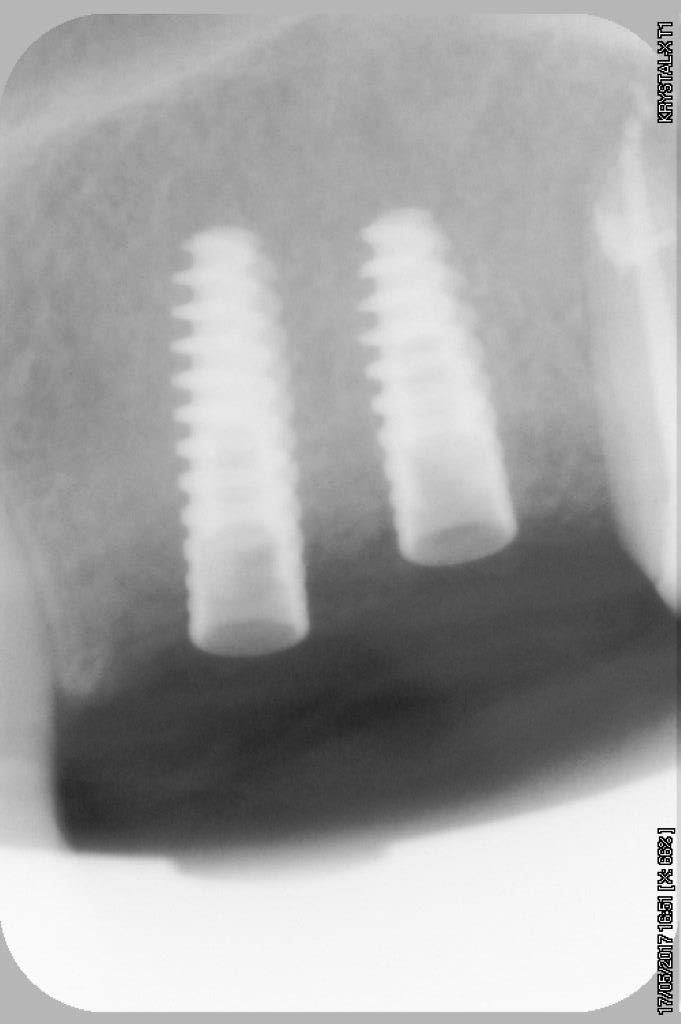

petit cas sympa ancien bridge très mobile....plutôt que d'extraire 25, j'ai déposé la couronne, retraité la dent stabilisation pendant deux mois puis séance d'ostéotension et ce jour pose de deux axioms PX 34120 après expansion...

comme je n'ai pas fait de décharges osseuse en vestibulaire, j'ai effectivement travaillé toute la longueur de la crête, mais, là j'ai ôtè les expanseurs avant de visser les implants car ce sont des PX qui ont un apex assez fin, pour des regular j'aurais pratiqué différemment.

par contre je suis passé par le stade implants lisse (34100 et 34120)